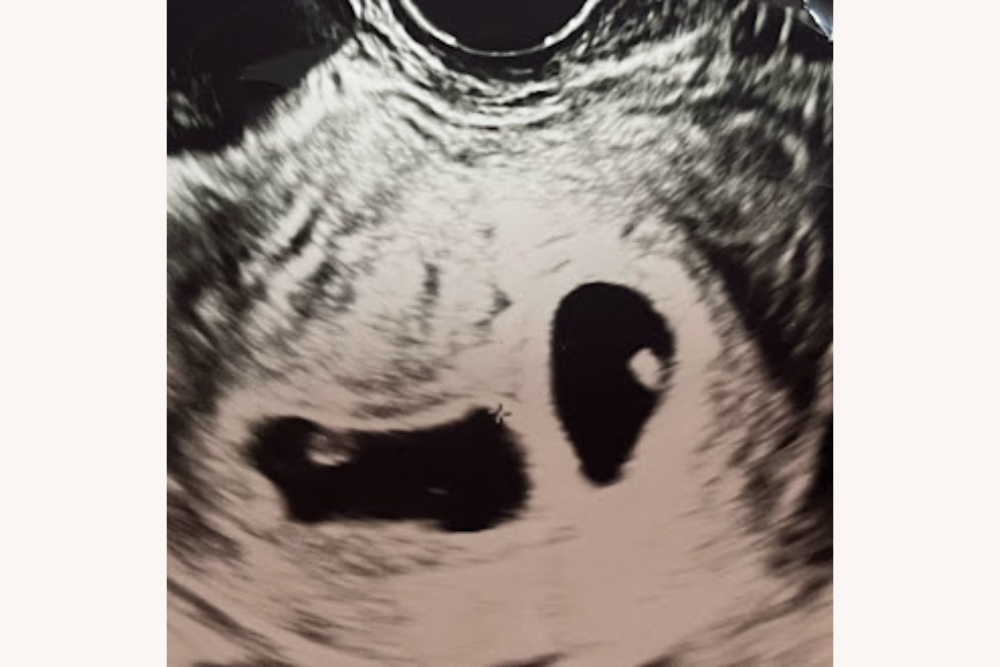

〈アナウンサー・坐間妙子さんの妊活〉巡り合わせがつないだ「2個胚移植」「双子妊娠」に奇跡を感じた【後編】